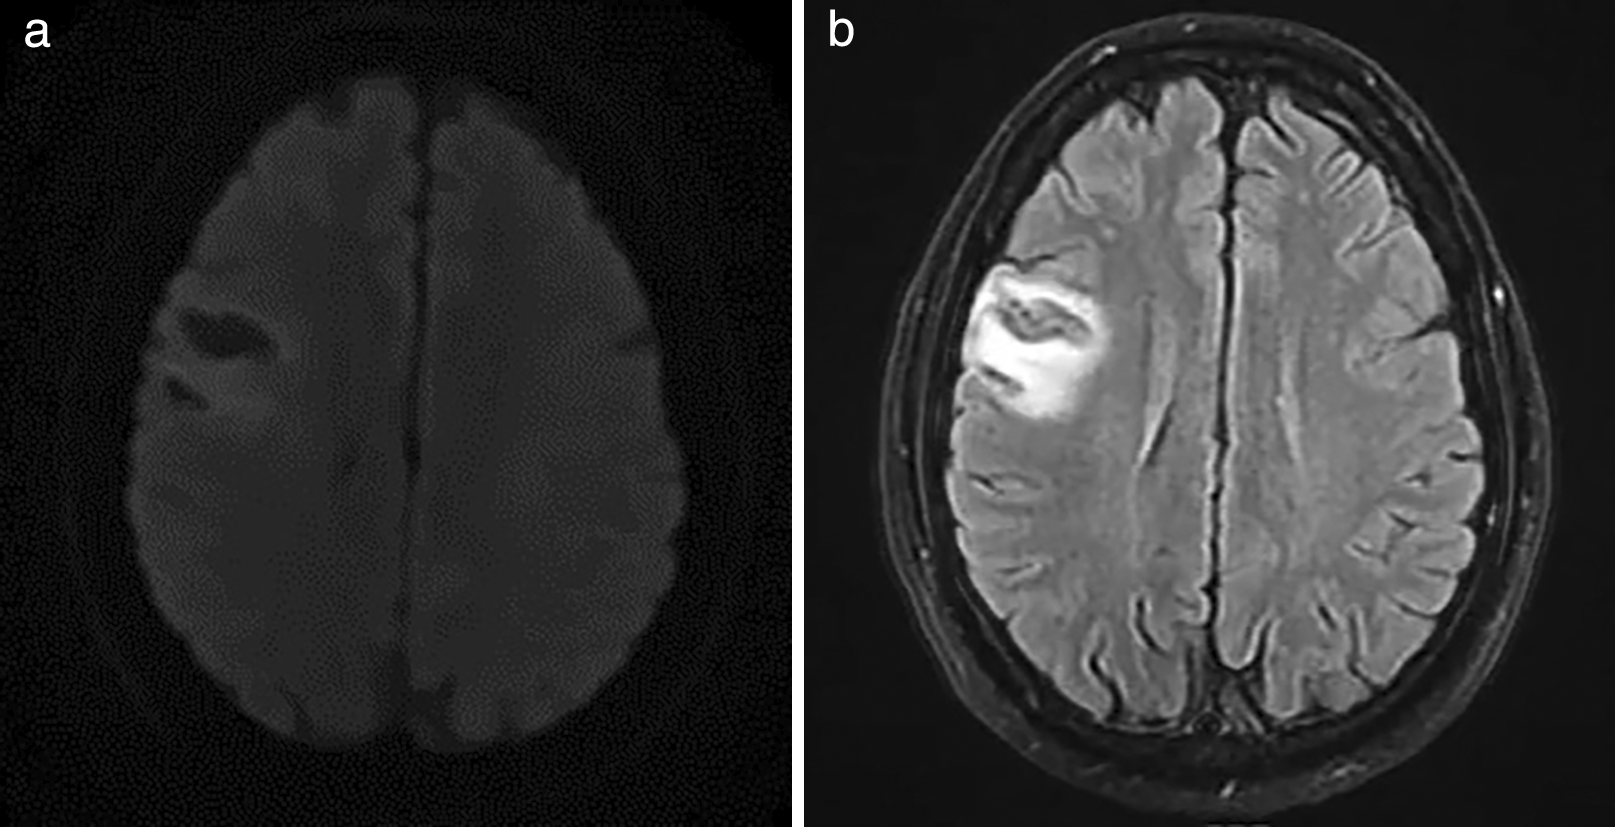

On physical examination he was found tachycardic, with normal oxygen saturation and blood pressure. The auscultation showed arrhythmic heart sounds and the rest of the general physical examination without significant alterations. On neurological examination the patient was alert, dysarthric, however, fluent, understand, name, and repeat; with preserved orientation. There was evidence of left central facial paralysis (Figure 1) and tongue deviation to the left (Figure 2). Left upper limb monoparesis 4/5 in muscle strength scale, with distal predominace at regional evaluation. Reflexes were symmetrical with normal gait and coordination. Complementary studies showed normal blood cell count, moderate hypokalemia, persistently elevated blood glucose levels and uroanalysis with glycosuria, with preserved renal function. Atrial fibrillation on electrocardiogram. Based on these findings, it was considered an acute stroke of probable cardioembolic etiology, which is confirmed with brain MRI that evidenced right frontal corticosubcortical lacunar image with gliosis in T2 and FLAIR sequence and that restrings in diffusion (Figure 3).